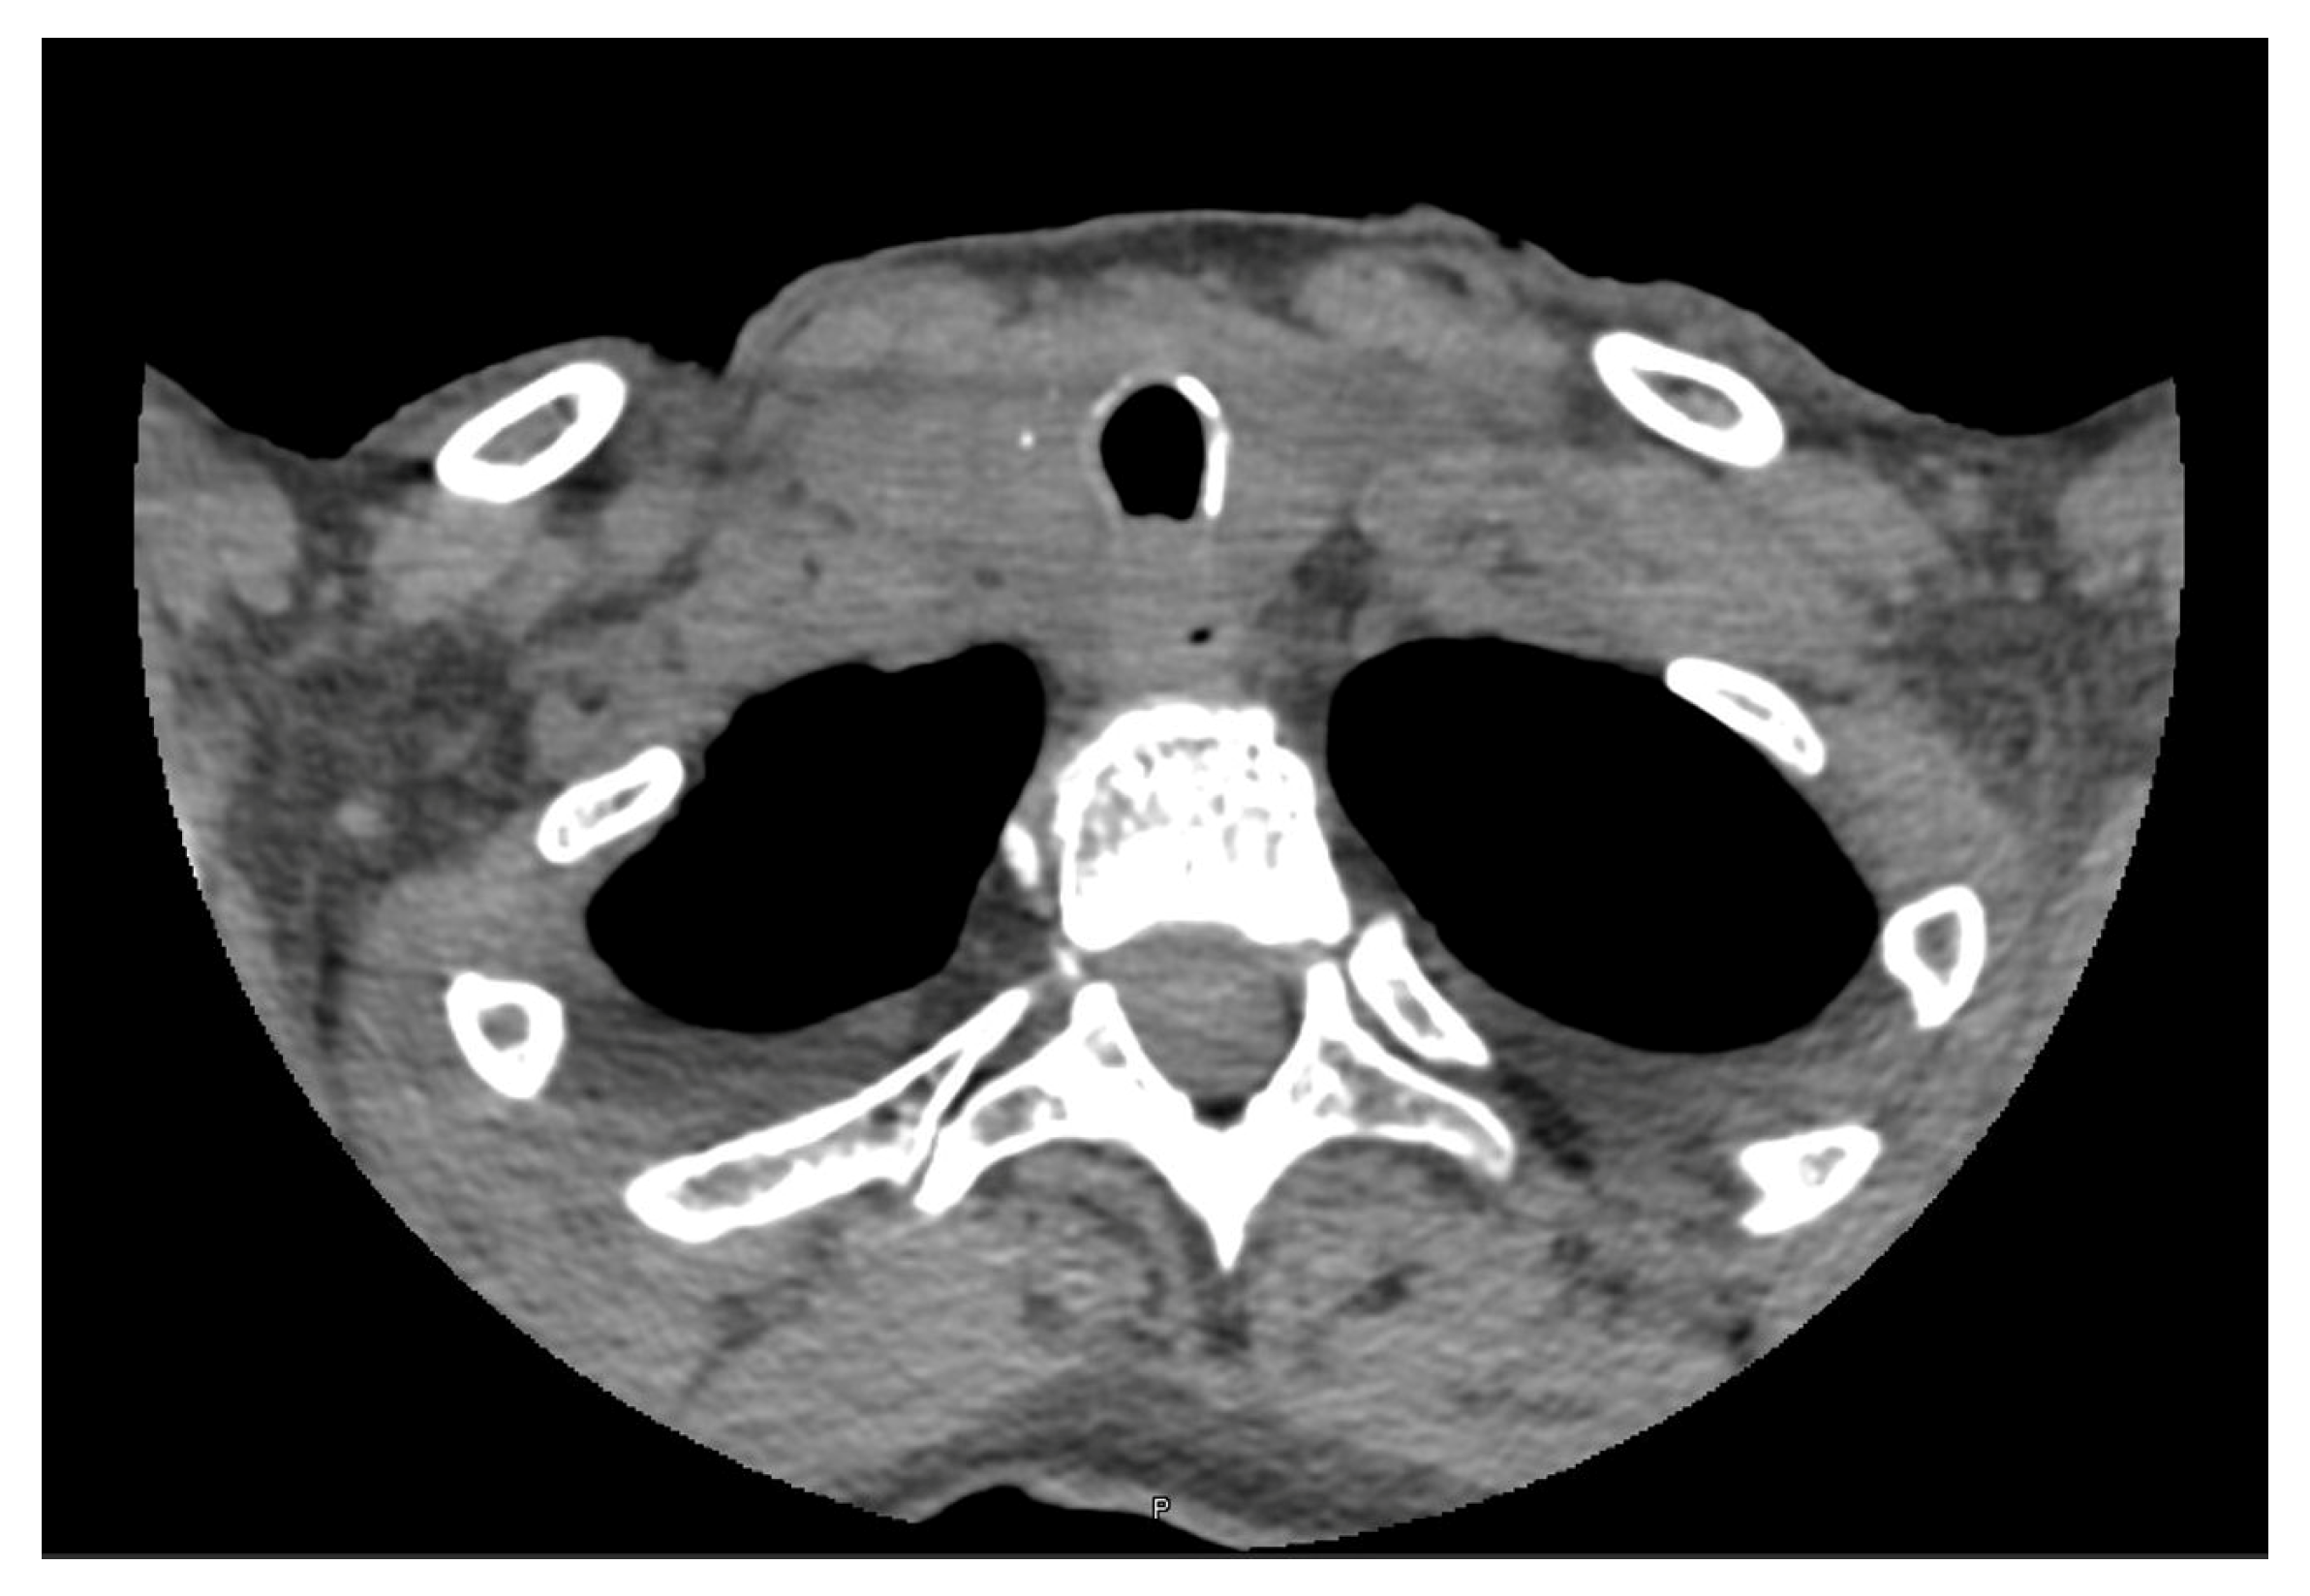

- Zhang, Y.; Xue, S.; Wang, Z.; Jin, W.; Chen, Z.; Chen, G.; Zhang, Q. Thyroid metastasis from breast cancer presenting with enlarged lateral cervical lymph nodes: A case report. World J. Clin. Cases 2020, 8, 838–847. [Google Scholar] [CrossRef]

- Lee, D.H.; Yoon, R.G.; An, J.K.; Woo, J.J. Ultrasonographic Features and the Diagnostic Role of Core Needle Biopsy at Metastatic Breast Cancer in the Thyroid gland: A Case Report. Taehan Yongsang Uihakhoe Chi. 2020, 81, 719–725. [Google Scholar] [CrossRef]